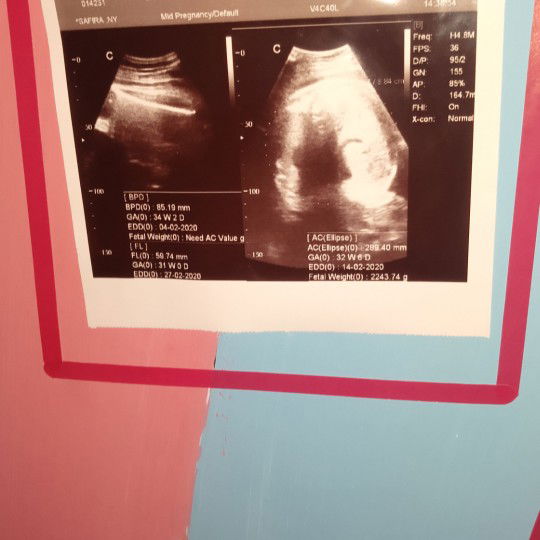

Tolong bantu jelaskan ya bun.. Magsdnya apa sih hasil usg saya kemarin kemarin. Dan umur kandungan saya itu berph bulan dan berph minggu ya. Terima kasih ???